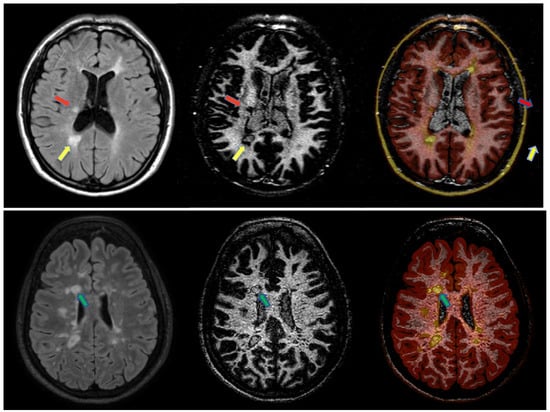

- White-matter selective DIR, FLAIR and T1w sequences were obtained using PAchieva scanners (, Philips Healthcare, Best, The Netherlands) at both MRI field strengths. For the sake of clarity, the WM-DIR sequence used in this work serves the same purpose as the GM-DIR sequence used in [8]. The DIR sequence is usually used for cortical lesion load assessment that involves mainly the GM tissue, whereas the WM-DIR sequence enhances the WM tissue and permits the detection of DRLs. Therefore, we will refer to WM-DIR in the forthcoming paragraphs.

- Magnetization transfer imaging (MTI) (3D FFE dual-echo sequence with a voxel size of 1.5 mm, TR6.4 ms, TE1/TE22.7/4.2 ms, FA 9°, with and without magnetization transfer pulses of angle 360°, duration 16 ms and offset frequency 1 kHz) at 3.0 T was acquired. The MTI acquisitions were used to compute magnetization transfer ratio (MTR) maps. First, the two echoes were averaged to improve the signal to noise ratio. MTR maps were computed as by Liu et al. [12].

3.3. 3.0. T MRI-Derived Tissue Features by Magnetization Transfer Ratio